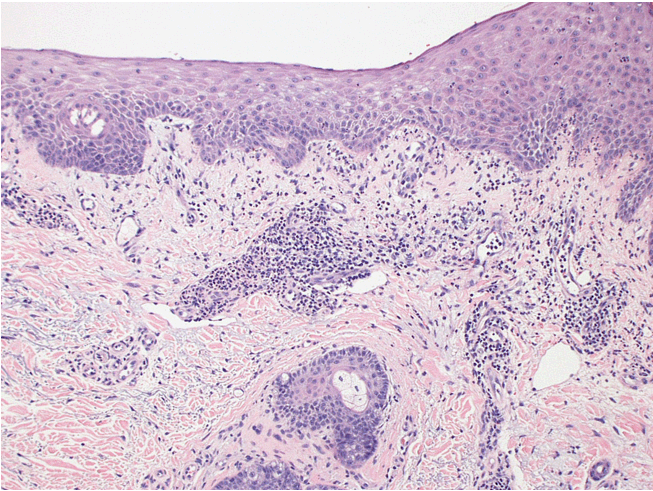

Two 6-mm punch biopsy were obtained from 2 separate lesions that demonstrated mixed superficial perivascular and interstitial dermatitis including many neutrophils. The dermoepidermal junction showed vacuolization of basal keratinocytes. Numerous clustered 5 mm to 2 cm clear smooth vesicles and tense bullae on the palmar surface with no nail involvement appreciated (Figure 3). The dermoepidermal junction of the lesion showed vacuolization of basal keratinocytes (Figure 4). Visualization under direct immunofluorescence (DIF) showed linear IgA deposit in the basement membrane zone (Figure 5).

Figure 4: The dermo-epidermal junction of the lesion showing vacuolization of basal keratinocytes (H&E stain, x100).